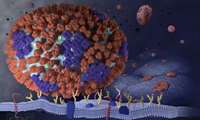

کشف ورودی مخفی ویروس HIV به بدن

مطالعه جدید دو دانشمند از دانشگاه شیکاگو نشان داده است که چگونه ویروس HIV هنگام حمله به سلول راه خود را به درون هسته مییابد.